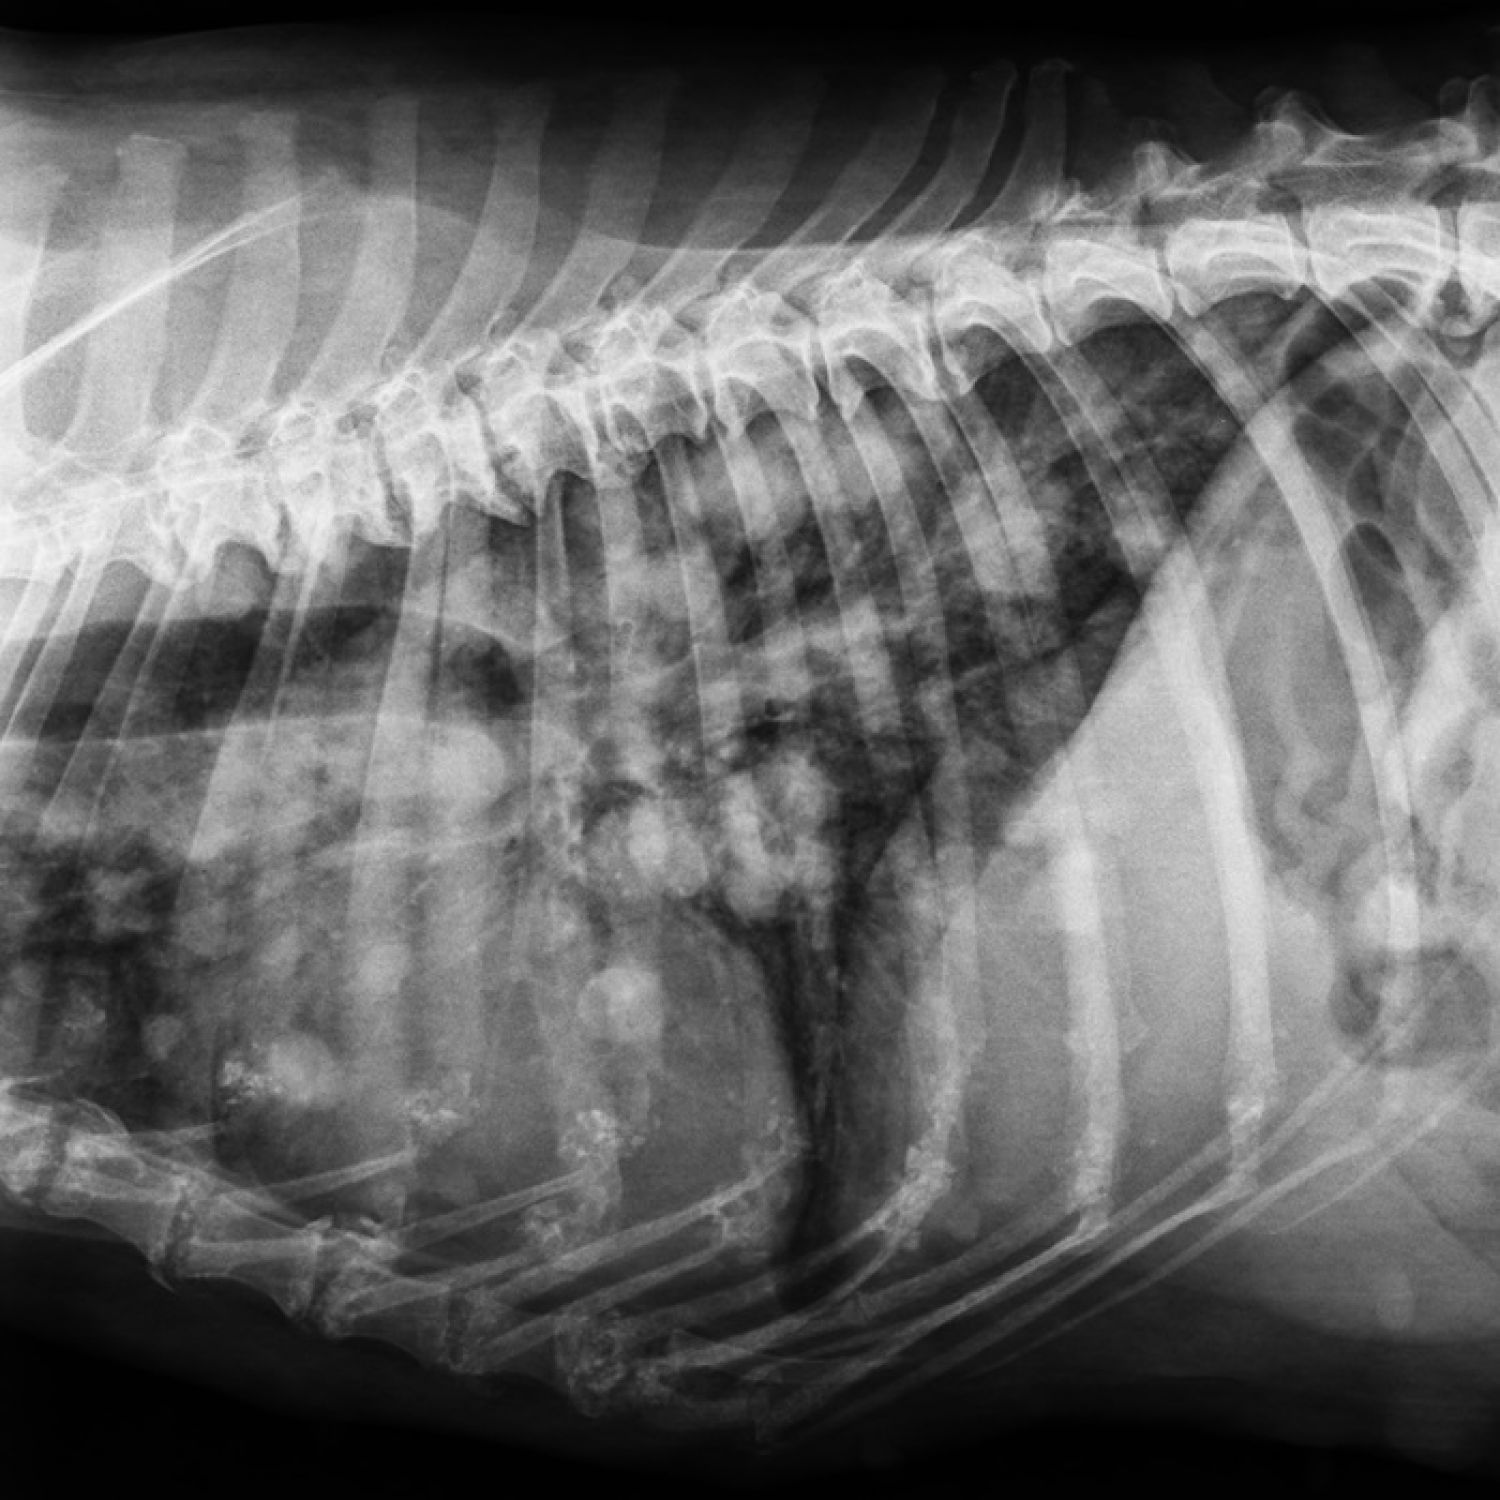

Aspect pulmonar nodular

Aspect pulmonar nodular. Formatiuni pulmonare suspect tumorale. Liza osoasa la nivel de sternebre si articulatii condro-costale. Spondiloza deformanta – proces tumoral pacient geriatric.